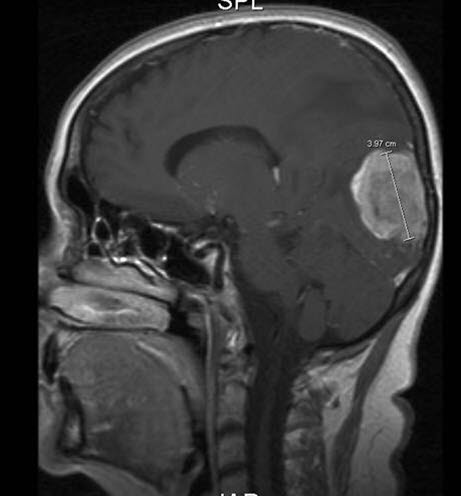

Foto: Radiologisk avdeling, UNNDet finnes mange ulike typer hjernesvulster. De deles inn etter hvilken celletype de minner mest om, hvor i hjernen de er lokalisert og hvorvidt de er godartet eller ondartet. Fordi hjernesvulster som er godartet kan være dødelig på grunn av sin plassering, risikerer man at skillet mellom en godartet og ondartet svulst blir kunstig.

Ved mistanke om hjernesvulst vil du bli henvist til sykehus for nærmere utredning. Her vil det bli tatt bildeundersøkelser av hjernen. MR er det viktigste hjelpemiddelet til å påvise hjernesvulst. Bildene blir tatt både med og uten kontrast (kontrast er et "fargestoff" som sprøytes inn i blodet og gjør strukturer lettere synlig på bildene fra undersøkelsen). Også andre bildeundersøkelser av hjernen kan være aktuelle som CT, ultralyd, PET.